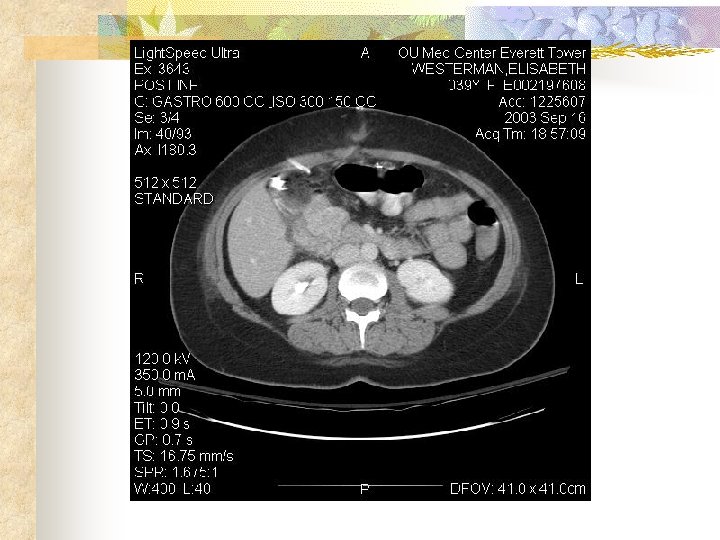

Gastrointestinal Stromal Tumors Case Presentation 2 HPI: 39 YO F transferred from outlying hospital 5 days S/P lap for UGI bleed with finding of duodenal mass. Bx c/w GIST tumor. Mass not resected. PMHx: Hepatitis C PE: Neg except for healing midline wound

Gastrointestinal Stromal Tumors Hospital course: Patient had no further UGI bleeding. Was seen in consultation by Med/Onc who recommended D/C until role of neoadjuvant therapy could be defined. Ultimately recommended against neoadjuvant therapy.

Gastrointestinal Stromal Tumors Hospital course: Underwent re-exploration and pylorus preserving Whipple on 10/27/03. Findings – mass in 2 nd portion of duodenum without evidence of metastases. Pathology – 4. 5 cm, hypercellular GIST tumor, c-Kit positive, no evidence of nodal metastases, uncertain malignant potential. Patient did well and discharged for followup by surgery and med/onc.